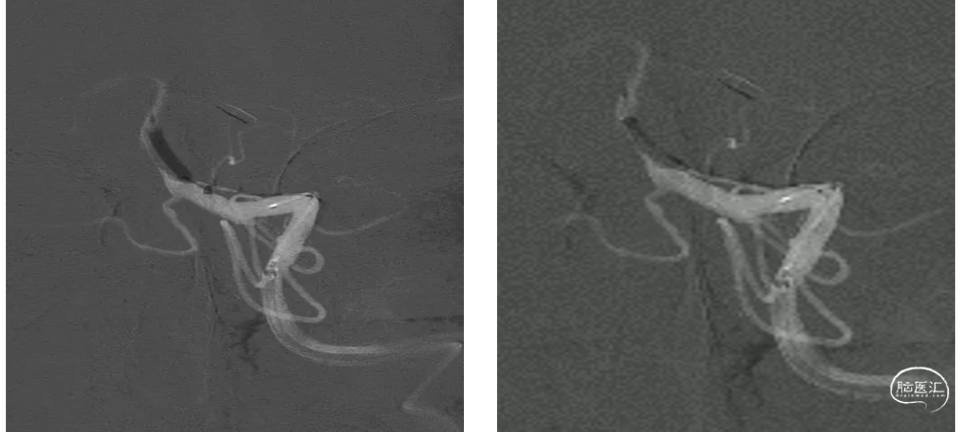

通过微导管将6*30mm Solitre支架置于M1段,静置后收扰支架尾部取栓,踹马桶抽吸ACE68抽吸导管。取出0.5Cm大小血栓和细条状血栓。

造影显示血管血流通畅达3A级,远端血管血流显影良好,未见明确逃逸征象。M1段残余狭窄约40~50%,不影响血流供应,未一期置入支架,服药观察。